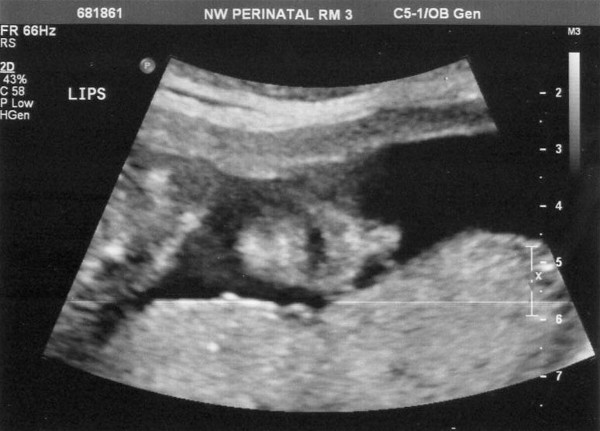

A prenatal appointment today gave these ultrasound pictures.

This one has the baby looking right at us. This angle makes it look like it has the head of an alien or something, but I'm quite sure it is a human head. (smile)

Here's a reasonably good profile.